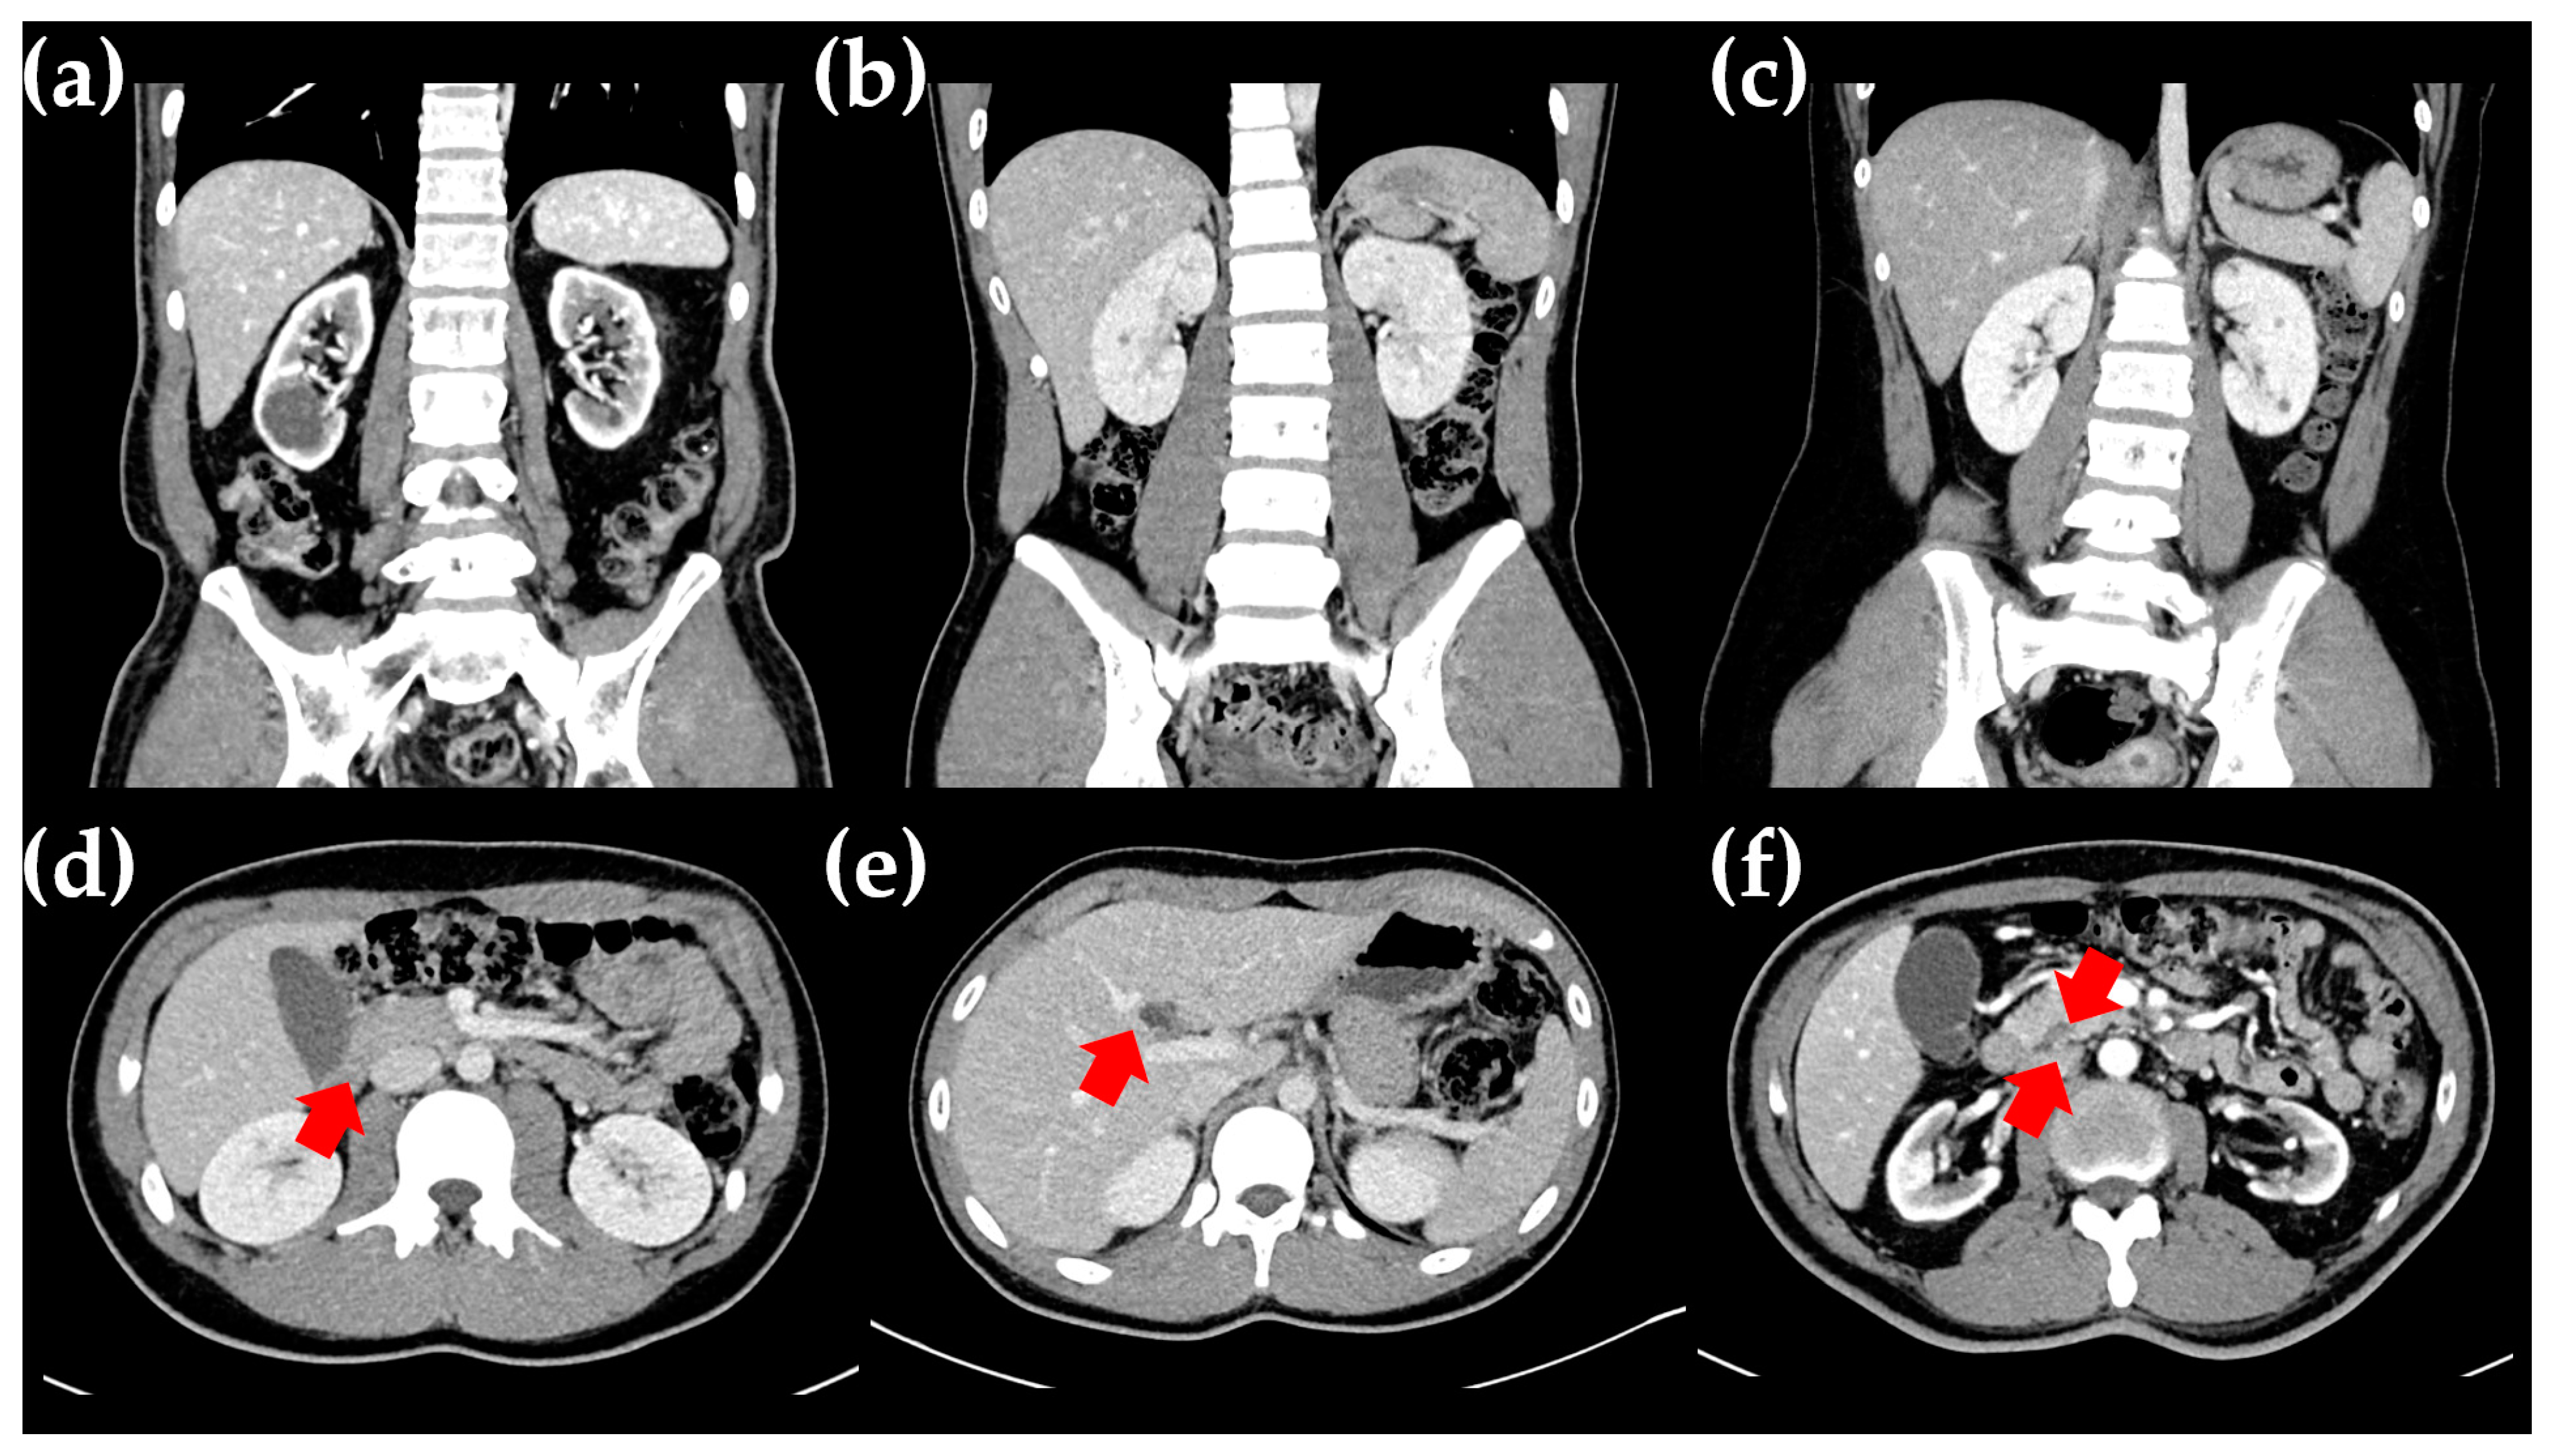

A 16-year-old Korean boy (V-1 in Figure 1a) presented at the Department of Pediatrics, Daejeon St. Mary’s Hospital (Daejeon, Republic of Korea), with a history of polyuria and polydipsia over the past month. He was the first child of non-consanguineous parents, and the pregnancy was uneventful. His growth percentiles were normal at birth. There was a family history of DM suggestive of an autosomal dominant pattern. Specifically, his grandfather (III-1 in Figure 1a) was diagnosed with DM in his late 20s, began dialysis in his 60s, and passed away at 70 due to a cerebrovascular event. His great-grandaunt (II-2 in Figure 1a) was diagnosed with DM in her 20s and passed away in her 30s due to a traffic accident. His aunt (VI-1 in Figure 1a) was diagnosed with DM at the age of 20, started dialysis at 50, and passed away at 55 due to sepsis as a complication of DM. The patient was 167 cm tall, weighed 63 kg, and had a BMI of 22.6 kg/m2 (60th percentile). Physical and neurological examinations revealed no abnormalities. His fasting glucose level was 301 mg/dL, and glycated hemoglobin (HbA1c) was 15.4%. Serum ketone bodies were elevated, and urine sugar was strongly positive. Autoimmune antibodies, including anti-GAD, anti-IAA, and anti-ICA, used for differentiating type I DM, were all negative. C-peptide and insulin levels were 2.13 ng/mL (normal range, 1.1–4.4) and 8.50 μU/mL (normal range, 1.90–23), respectively. Abdominal computed tomography (CT) revealed bilateral renal cysts, a hepatic cyst, and agenesis of the dorsal pancreas, with no abnormalities detected in other abdominal organs (Figure 2b,e,f). Based on clinical, imaging, and biological variables, MODY5 was suspected due to young-onset DM, normal BMI, renal cysts, insulin secretion dysfunction, negative autoantibodies to IA-2, and an HNF1B score of 14, which is a pivotal tool for rational genetic testing [7]. He was treated with intensified insulin therapy (total 0.2 units/kg), leading to improved glycemic control. He showed no signs of diabetic retinopathy, neuropathy, or nephropathy.

Figure 2.

Radiologic findings in the proband and his family. (a–c) Abdominal CT findings show renal cysts in the proband’s father (a), the proband (b), and the proband’s sister (c). (d–f) The cortical thinning of both kidneys and atrophic changes in the pancreas (d) were found in the proband’s father, while a hepatic cyst (e) and agenesis of the dorsal pancreas (f) were found in the proband. The tail of the pancreas was not visible on consecutive axial slices, showing only the head and body of the pancreas (indicated by red arrow).

The proband’s father (IV-3 in Figure 1a), a 53-year-old man, was diagnosed with DM at the age of 15, requiring insulin injections thereafter. At the time of diagnosis, his fasting glucose level was 398 mg/dL, and his HbA1c was 17%. He was diagnosed with autoantibody-negative type I DM. Around the age of 35, he developed diabetic triopathy (retinopathy, nephropathy, and neuropathy), undergoing vitreoretinal surgery at 39. His renal function progressively declined, leading to end-stage renal disease in his late 40s, necessitating renal transplantation at 50. An abdominal CT scan revealed bilateral parenchymal thinning with cysts in both kidneys and pancreatic atrophy extending from the neck to the tail (Figure 2a,d). An ultrasound performed at age 39 showed a right renal cyst with a diameter of approximately 1 cm. However, a CT scan conducted at age 50 revealed that the cyst had enlarged to about 3 cm, accompanied by progressive renal atrophy.